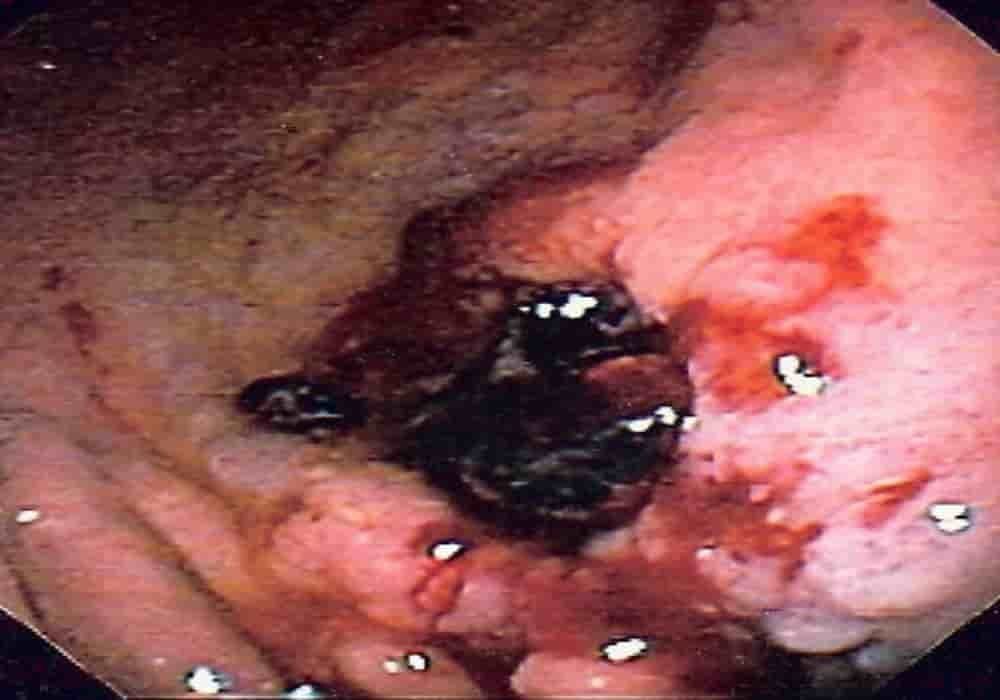

Muntah darah (juga disebut hematemesis) adalah dikeluarkannya darah melalui mulut

Jika seseorang mulai muntah darah, kondisi serius yang dikenal sebagai hematemesis dapat diindikasikan. Hematemesis adalah kondisi yang sangat berbahaya di mana seseorang mengalami pendarahan di dalam, dan darah keluar bersamaan dengan muntahnya.

- Muntah berwarna coklat atau hitam.